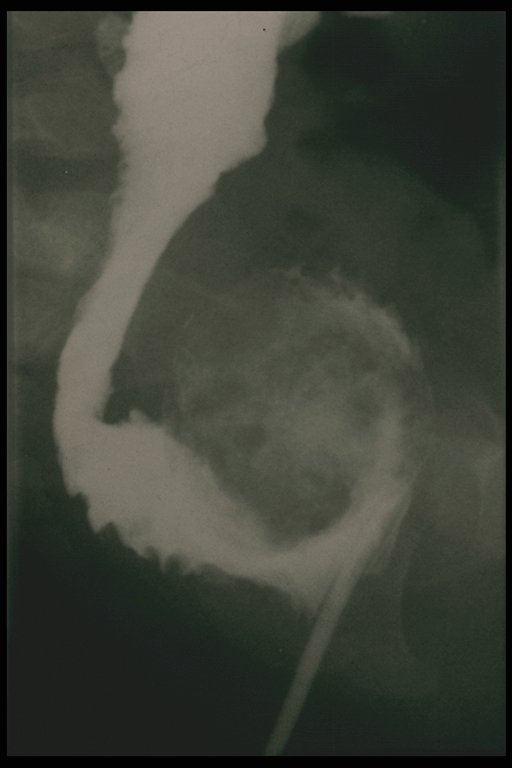

Contrast study showed fecaloma in the rectal reservoir after Duhamel's operation